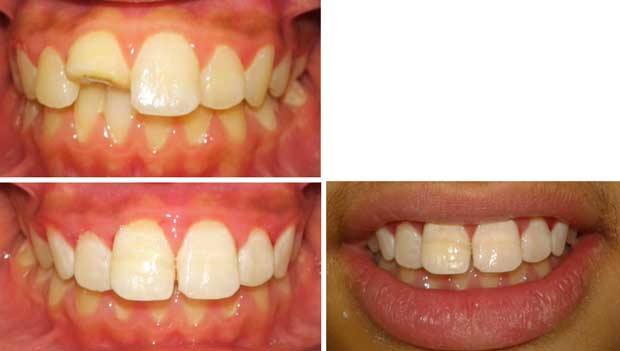

Cas clinique 3 :

Une jeune fille âgée de 11 ans s’est présentée au service des urgences du CCTD de Casablanca, suite à une chute à l’école survenue 7 heures auparavant. L’examen clinique endobuccal a montré la présence d’une fracture coronaire avec exposition pulpaire de la 11. Le fragment fracturé était entier, conservé dans de l’eau et ramené pour le collage. La dent étant mature, un traitement canalaire fût réalisé suivi du collage dentaire par la technique de chanfrein externe.

Les étapes de réalisation de la technique de collage sont illustrées par les figures 14 à 22.

Fig 22 : Cas clinique avant et après collage. |